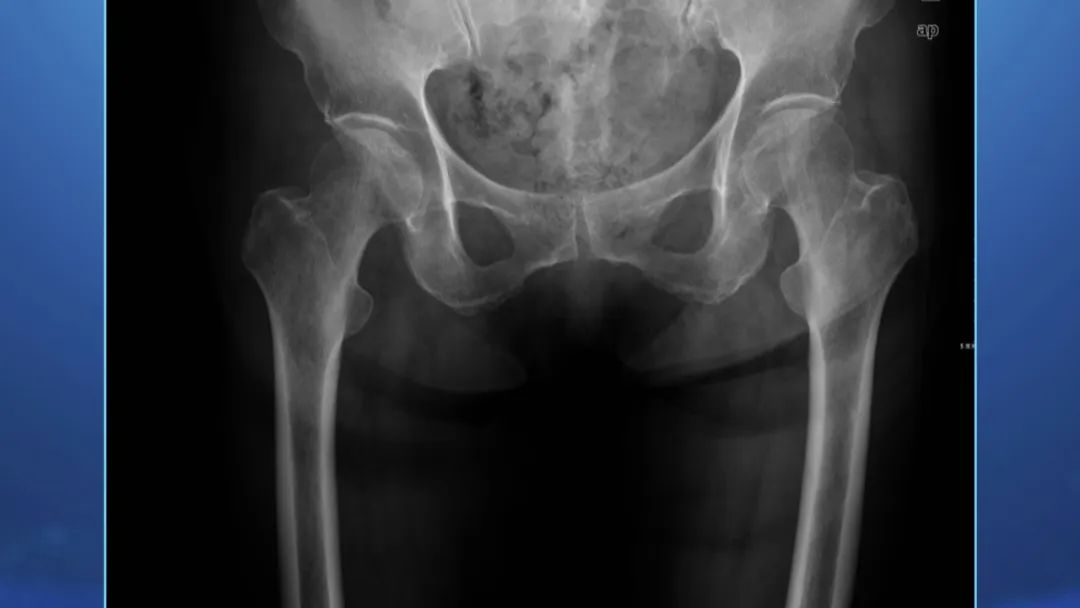

有种骨折,即使骨折了还“能动”,甚至拍片子都可能看不出来!专家提示,这种骨折让他们骨科医生都非常头疼,这究竟是怎样一种骨折?老年人又该如何避免呢?更多精彩内容敬请关注本期节目。

专家提示,这种骨折有四种类型,其中第一种叫“嵌插型骨折”,几乎没有移位,因此即使照片子也可能看不出来。但是这种骨折非常危险,被称为是“人生的最后一次骨折”,那么到底该如何发现它呢?更多精彩内容敬请关注本期节目。